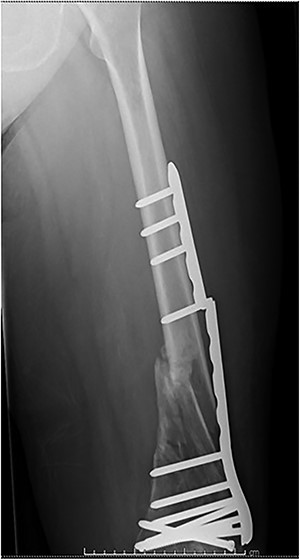

The cases of failure are here examined in more detail. Case 1 (Figs 1 and 2): this active gentleman was paddleboarding off the Llŷn peninsula when he was knocked onto his side by a wave.

Fracture above plate tip following successful union for Case 1.

Clearly, this has occurred following on from successful union. Despite a sound original fixation, the rigid construct has acted as a lever-arm to produce a fracture above the plate tip. In long spiral fracture configurations such as this, antegrade intra-medullary nailing could be considered as the primary treatment modality.